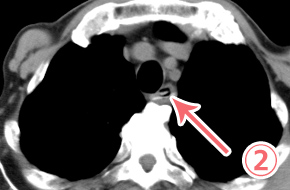

内視鏡で、胃粘膜に刺⼊しているアニサキス発⾒。

捕まえて引っ張っています。その後摘出されました。